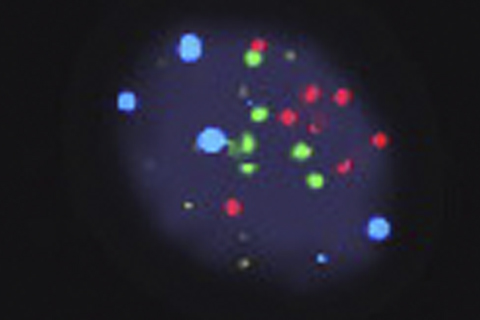

Urine cytology - fluorescence in situ hybridization